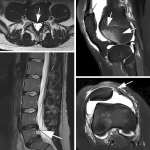

Low-field MRI: The imaging solution radiologists haven't learned to trust

At the 2025 ESMRMB Annual Meeting in Marseille, speakers made a strong case for what remains an outsider in radiology: low-field MRI. Despite its affordability, improved performance, and reduced environmental footprint, the technology continues to face scepticism – not from regulators or patients, but from radiologists themselves.